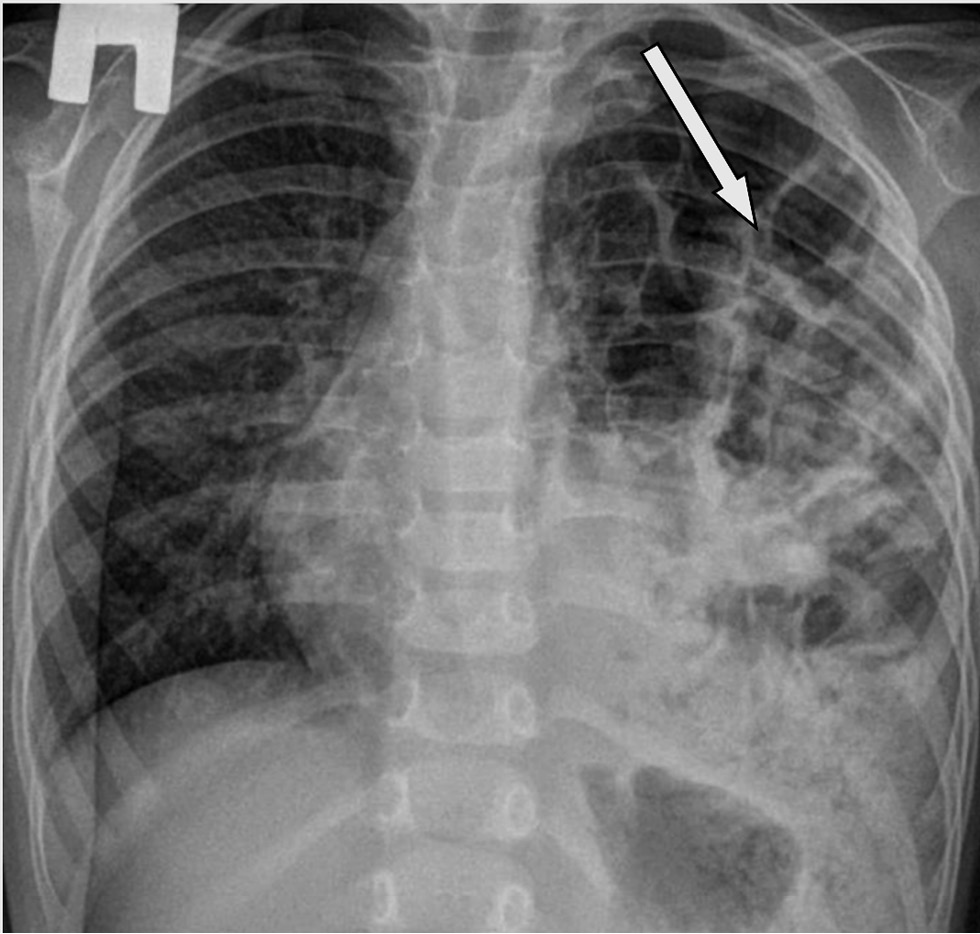

При компьютерной томографии (КТ) органов грудной клетки линия диафрагмы не визуализировалась слева, обнаружено смещение средостения вправо, в левой плевральной полости — петли тонкой и толстой кишки, селезёнка и часть желудка. Диагноз «диафрагмальная грыжа слева» был подтверждён (рис. 2, a–c). Учитывая наличие сомнений в диагнозе (на КТ не визуализировалась диафрагма), возникло подозрение на аплазию диафрагмы, было принято решение провести боковую торакотомию слева. При выборе оперативного доступа, хирурги решили провести боковую торакотомию слева.

Рис. 2. Мультиспиральная компьютерная томограмма органов грудной клетки с контрастированием: a — фронтальный срез; b — сагиттальный срез; c — аксиальный срез.

Fig. 2. Multislice computer tomogram of chest organs with contrast: a — frontal section; b — sagittal section; c — axial section.